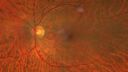

Last additions - Cotton wool spots following Cario-pulmonary bypass 58 year old man The patient had emergency thoracotomy about 3 weeks ago he had an aortic dissection with a root aneurysm. It had dissected down to the iliacs. The patient had a thoracotomy and aortic valve replacement and large aortic graft. He did well post-op and then he noticed when he got out of the hospital that the right eye was worse. The right eye had been weaker than the left even after LASIK in the early 2000s. Over the last 7 days now that he has noticed that the right eye is getting better each day. He is on coumadin and will be on it for 3 months. He noticed 10 days ago that there was some graying in the right eye which is now getting a little bit better.

Cotton Wool Spots following cardio-pulmonary bypass28 viewsThe patient had emergency thoracotomy about 3 weeks ago he had an aortic dissection with a root aneurysm. It had dissected down to the iliacs. The patient had a thoracotomy and aortic valve replacement and large aortic graft.Mar 15, 2026